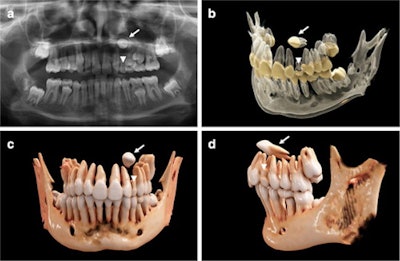

An 11-year-old girl with a horizontally impacted canine (white arrows) and a persisting deciduous canine (white arrowheads). (a) An x-ray of the girl's mouth. (b) Semitransparent reconstruction parameters are used to visualize bone, teeth, and different dental tissues. (c and d) The teeth and bone tissue with a soft kernel show a photorealistic visualization in both a frontal and lateral view.Recently, cinematic rendering, a technology that uses data derived from CT and conebeam CT images, has been used as an alternative approach for visualizing volumetric medical imaging data. Since its introduction, cinematic rendering has found applications in medical clinical research and anatomical education, but it has not been tailored to dentistry. Currently, there is only limited research on this technology in dentistry. Mainly, cinematic rendering has focused on fractures and carcinoma as maxillofacial indications, the authors wrote in the report posted on 4 April.